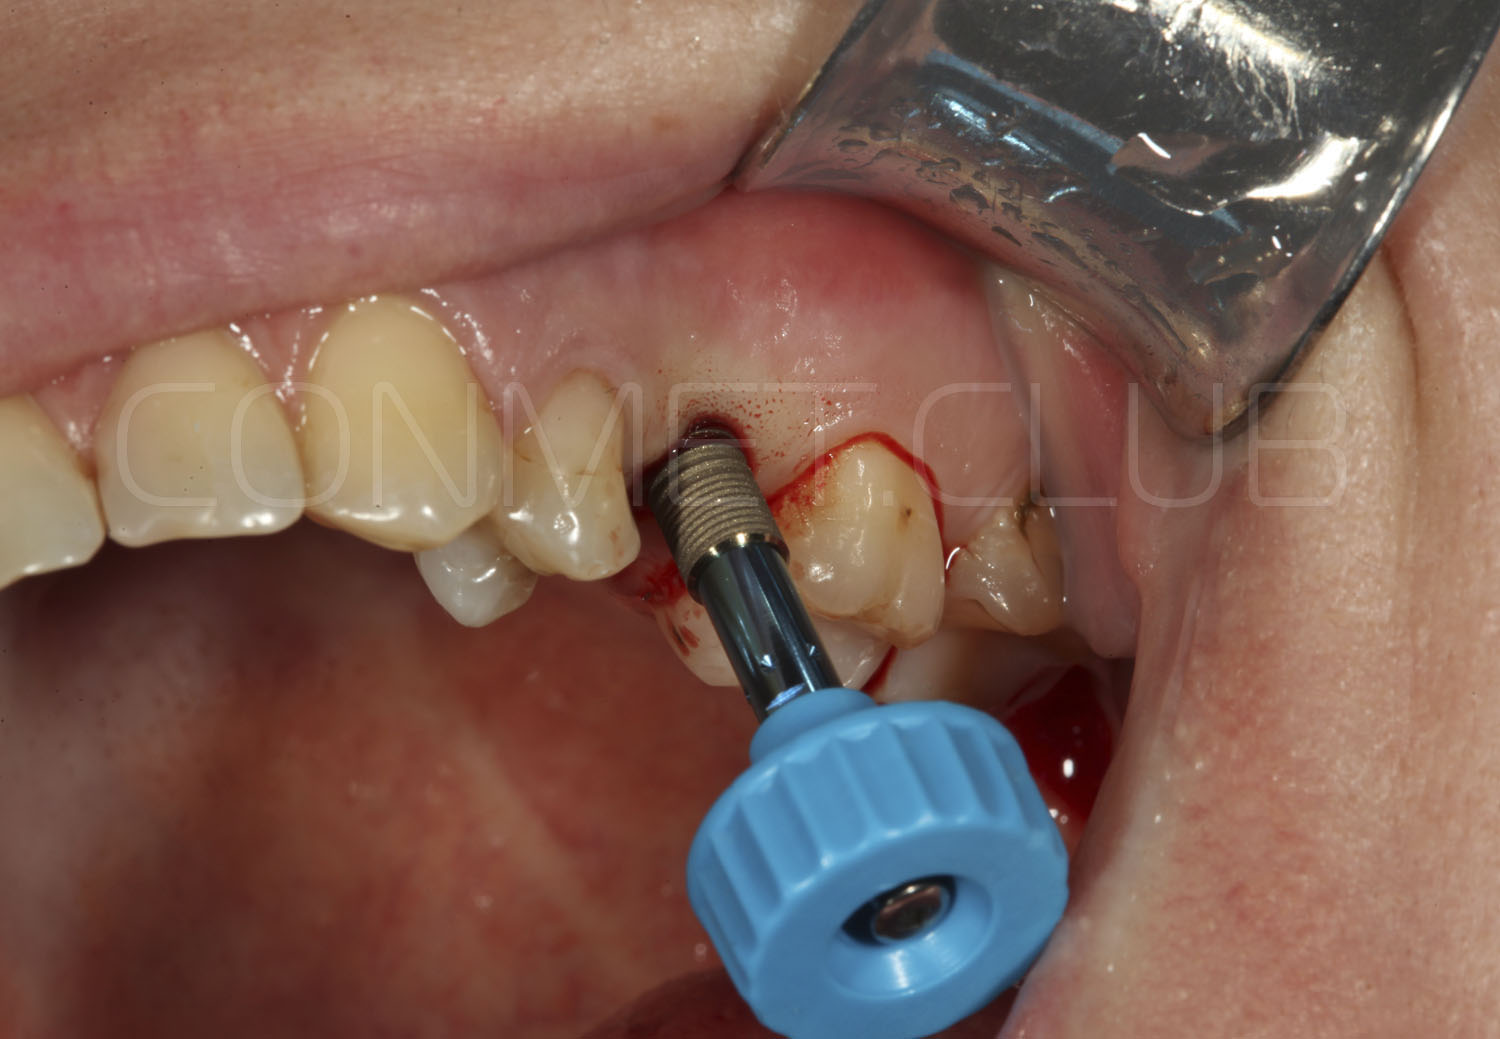

Имплантат устанавливается в подготовленное ложе. Так как не производится широкого откидывания слизисто надкостничных лоскутов и операция проводится через маленькое перфорационное отверстие, кровоточивость и сама операционная травма - минимальные.

После установки имплантата Конмет,  на период интеграции (6-8 недель), фиксируется винт заглушка. В подобных случаях швы никогда не накладываются, а пефорационное отверстие в слизистой оболочке закрывается дентальным Солкосерилом.